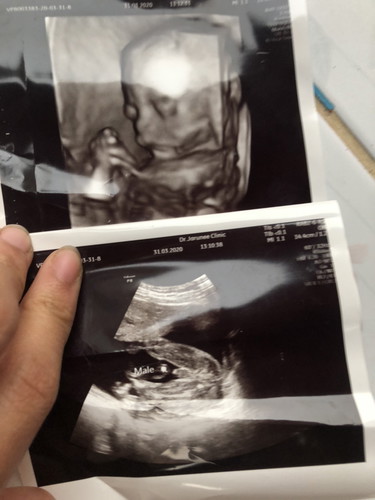

19สัปดาห์4วัน

อยากได้ผู้หญิงเพราะพี่คนโตเป็นผู้ชาย สรุปน้องคนเล็กก็เป็นน้องชายจร้าาา กระจู๋พุ้งมากลูกกก ?? 1.คนโตชื่อไอโฟน น้องคนเล็กชื่ออะไรดีนะ?

เหมือนกันเลยค่ะแม่ อยากได้ผู้หญิงเพราะคนพี่เป็นผู้ชาย แต่ไปซาวด์ตอน 18w ได้ผู้ชายอีกแล้ว ยังไงก็รักค่ะ

ทำไมเวลาซาวหน้าจอมันไม่ขั้นว่า Male. เหมือนคนอื่นๆคะ เเล้วเเต่จอภาพรึป่าว

ที่ขึ้นเพราะคุณหมอพิมในขณะที่ซาวค่ะ